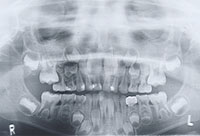

اما بالنسبه ان ليش لسه ماطلع اول شي رح بنقل لك مواعيد ظهور الاسنان مع صوره عشان تحددي اى سن قصدك بالزبط لانه كل سن ايله موعد ظهور والحل بسيط اختى خليها تروح عند اى دكتور اسنان ويعمل لها اشعه لاسنان ويشوف السبب ويشوف اذا اصلا موجود او ولا وان شاءالله يكون موجود

الأسنان الدائمة:-

نوع السن ميعاد البزوغ (سنوات)

القاطع المركزي 6-8 سنوات

القاطع الجانبي 7-9

الناب 11-13

الناجذ الأول 10-12

الناجذ الثاني 12-14

الضرس الأول 6-7

الضرس الثاني 12-14

الضرس الثالث 17-25

شوفي هي صوره اشعه للطفل بيظهر فيها الاسنان الدائمه والؤقته وان شاءالله بتتطمنوا عنها وبطمنني